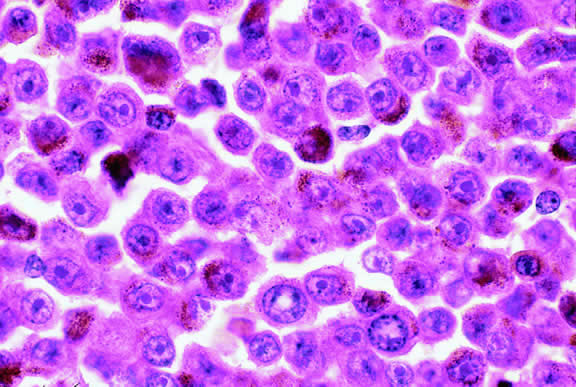

Epithelioid melanoma cells comprise the poorly differentiated end of the cytologic spectrum. Melanomas that contain epithelioid cells have a poorer prognosis. The term epithelioid meaning epithelial-like reflects the fanciful resemblance of the tumor cells to the cells of simple epithelia. Epithelioid cells have abundant cytoplasm and are often polygonal in shape (Fig. 33). They have distinct cytoplasmic margins, are poorly cohesive, and do not grow as a syncytium. The nuclei of epithelioid cells are usually round or oval and often appear vesicular because of margination or clumping of the chromatin along the inner side of the nuclear membrane. Epithelioid melanoma cells also have prominent nucleoli that are often large and reddish purple. Variants of epithelioid cells include relatively uniform small epithelioid cells (Fig. 34) and bizarre tumor giant cells that may appear wildly anaplastic (Fig. 35).

Fig. 33. Epithelioid melanoma cells. The cytoplasmic margins of these large, poorly cohesive epithelioid melanoma cells are easily discernible. Epithelioid cell nuclei are typically round and have peripheral margination of coarsely clumped chromatin. Epithelioid cells usually have prominent reddish purple nucleoli. They typically are polyhedral in shape and have copious amounts of cytoplasm. (Hematoxylin-eosin, × 250.)